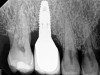

Fig 5. In this patient, deep probing depths, suppuration, and bleeding on probing were identified.

Figure 5

Fig 6. Radiographic bone loss confirmed the diagnosis of peri-implantitis.

Figure 6